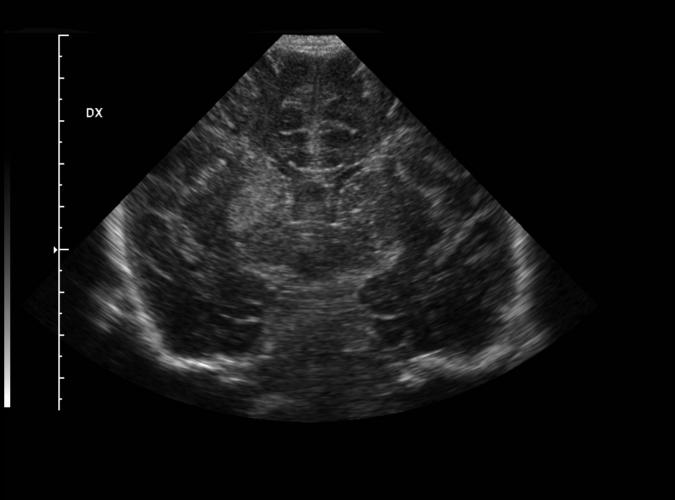

Barnskalle. Född vecka 40, asfyxi.

Högersidigt ekorikt område som tolkas som ischemi.